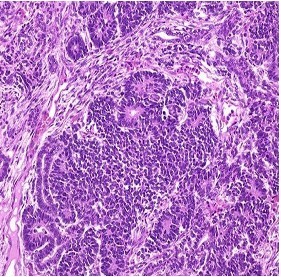

Wilm’s tumor= Nephroblastoma

Embryonal tumor from nephrogenic nests

Abdominal mass does not cross midline

Chromosome 11 (11p); WT1 and WT2 genes overexpressed

- 85% of pediatric renal tumors

Associated with dysmorphic tumor syndromes in 10% of the cases:

– Wilms-Aniridia-genital anomaly-retardation syndrome

– Beckwith-Wiedemann syndrome (abdominal wall defect, macroglossia,macrosomia)

– Hemihypertrophy

– Denys-Drash syndrome (pseudohermaphroditism glomerulopathy)

– Familial nephroblastoma

Gross: Large round demarcated tumor with tan-grey, fleshy, hemorrhagic surface

Histo: Mixture of immature renal elements

Hematoxylin-Eosin (H&E stain): Blastema, Stroma and Epithelia.

- Blastema= small blue cells in solid nests.

- Hypocellular stroma with myxoid spindle cells.

- Epithelia arranged in tubules